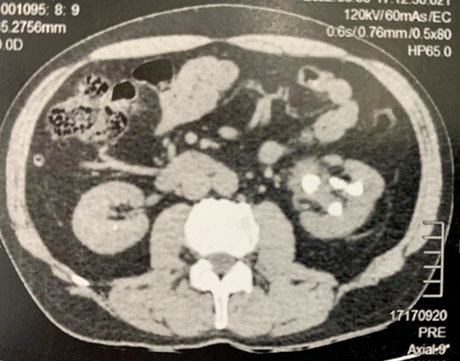

Caso do Mês: Set/2022: Tratamento de Cálculos Renais pela técnica de Dusting

Tratamento de Cálculos Renais pela técnica de Dusting com Thulium Fiber Laser

Litíase Renal - Thulium

-62 anos, masc.

-Antecedente de cirurgia percutânea há 8 anos

-Dor lombar esquerda recorrente

Imagem Inicial e final: